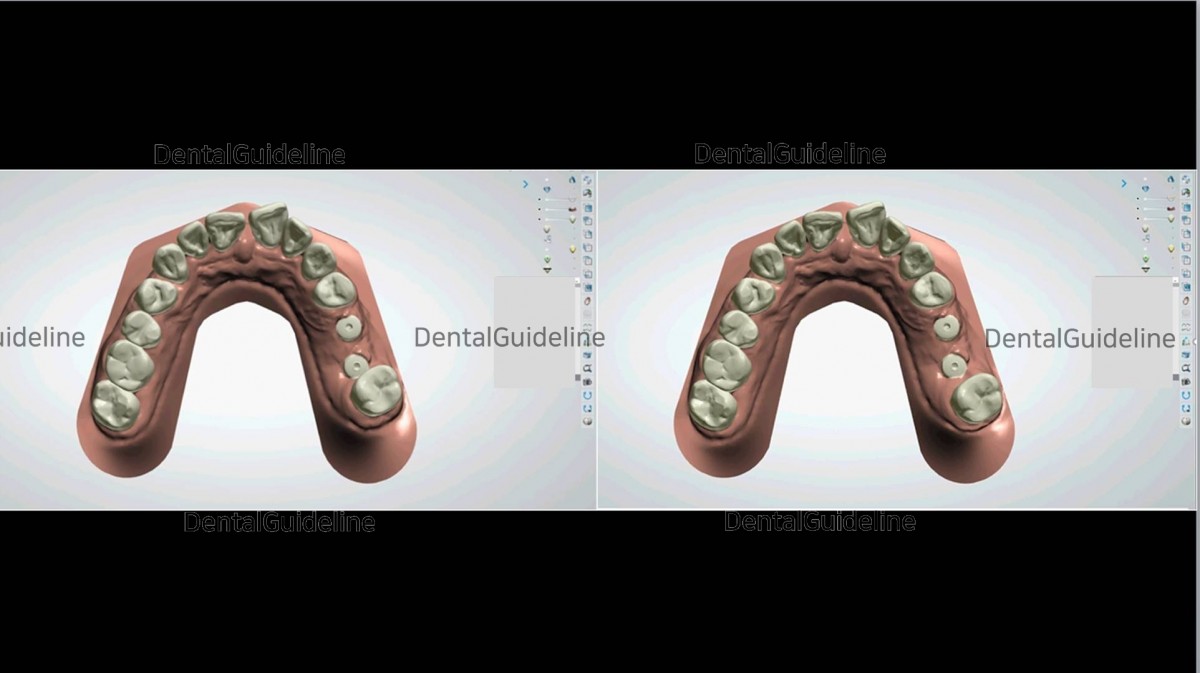

9. Intra-oral scanning was done to fabricate a tooth-positioning appliance for the 2nd molar distalization.

10. 2nd molar movement simulation – before and after